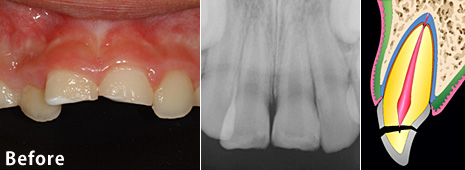

Before

| 主訴 | 歯冠破折 |

| 年齢・性別 | 8歳 男子 |

| 治療期間・回数 | 複数回 |

| 治療方法 | 見えていた歯髄の表層をとり(断髄し)、歯髄の傷が治りやすい薬で傷口を保護しました。その後、折れた破折片を、修復材にてもとの歯に接着しました。 |

| 費用 | 保険適用 |

| デメリット・注意点 | 定期的なレントゲンでのチェックが必要 |